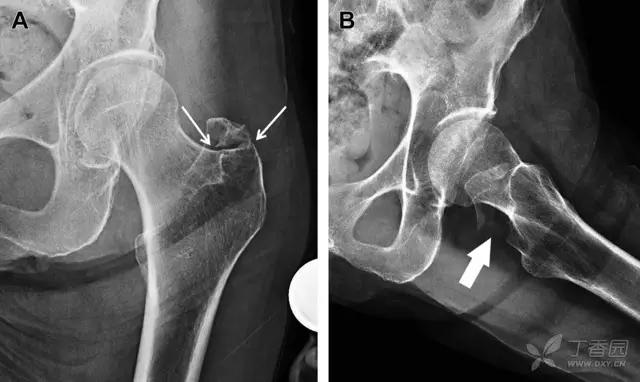

股骨颈应力性骨折

股骨颈应力性骨折在参加耐力运动的运动员中常见,且常发生在股骨颈压力侧。股骨颈基底部发现一垂直于骨皮质的线性硬化带可诊断这种类型的疲劳性骨折(图 8)。

图 8 长跑运动员股骨颈应力性骨折。X 片(A)和冠状位 CT 多维重建(B)图像示穿过股骨颈内侧皮质中的透亮区(箭头),周围硬化。骨折垂直于皮质

股骨颈张力侧的应力性骨折有可能发展为完全骨折(图 9)。

图 9 进食障碍患者股骨颈应力性骨折的张力侧。A 正位片示股骨颈完全骨折。B 2 周前的 X 片示局部骨量减少,正是后来发生骨折的位置(箭头)